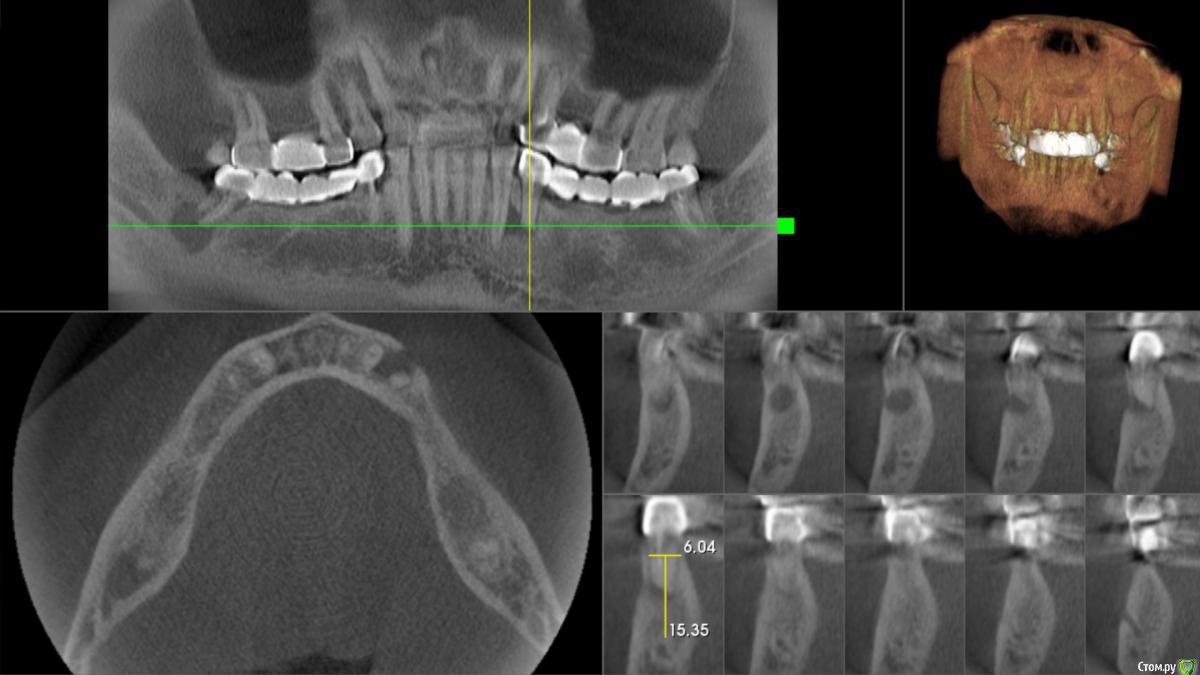

Foxtrot Опубликовано 27 мая, 2018 Поделиться Опубликовано 27 мая, 2018 Здравствуйте, коллеги. Пациент М 49 лет, планируется удаление зубов: 47, 44, 34 и установка 6-ти имплантов на н/ч. Смущает ситуация в области 34;44. Стоит ли идти на одномоментную имплантацию или лучше удалить и подождать? Ссылка на комментарий